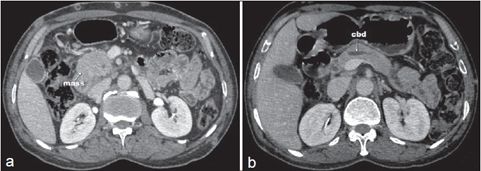

影像学检查: X射线检查显示关节正常。腹部计算机断层扫描显示不明确的低密度肿块,大约2.2×2.7 cm,胰头部的范围为2.6 cm,胰管扩张至4 mm (图3a和b)。皮下平面也有多个软组织结节。

图3 CT显示:(a)胰腺头部的肿块;(b)胆总管